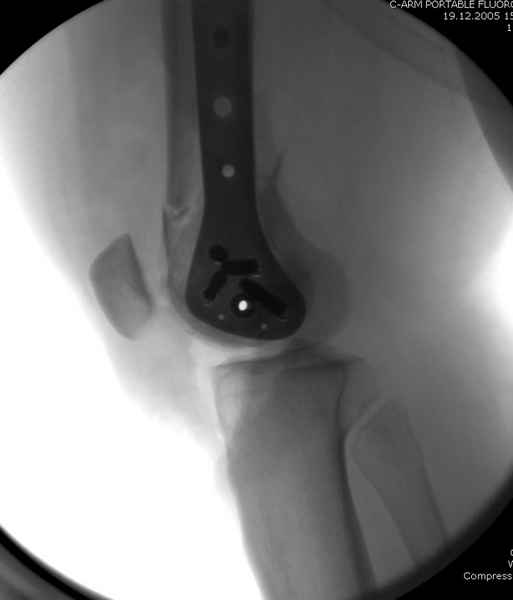

При наличии различных имплантов, любые варианты: слева (полу) открытым - мининвазивным, а справа закрытым интрамедуллярным методом, его считаем более чем приемлемым для фиксации данных переломов.

Проксимальная и дистальная блокировка, независимо от техники введения штифта, ретроградно или антеградно, гарантирует сращение сегментарных переломов бедра без укорочения. Штифты диаметром 12 мм с блокировкой сверху и вниз двумя шурупами выдерживают вес 75 кг больного, что позволяет раннюю профилактику контрактур.

Погоня за "красивой рентгенограммой" не всегда оправдана для фиксации кости, где имеется массивное мягкотканое покрытие. Если так уж хочется исправить положение кости, то при наличии ЭОП, большие костные фрагменты могут быть развернуты или приближены к основному фрагменту методом применения Joystick.

Из-за вариабельности установки дистальных шурупов и возможности перкутанного введения проксимально предпочитаем DePuy Polyax, хотя на сегодняшнем маркете множеств вариантов фиксации дистального бедра перкутанном методом.